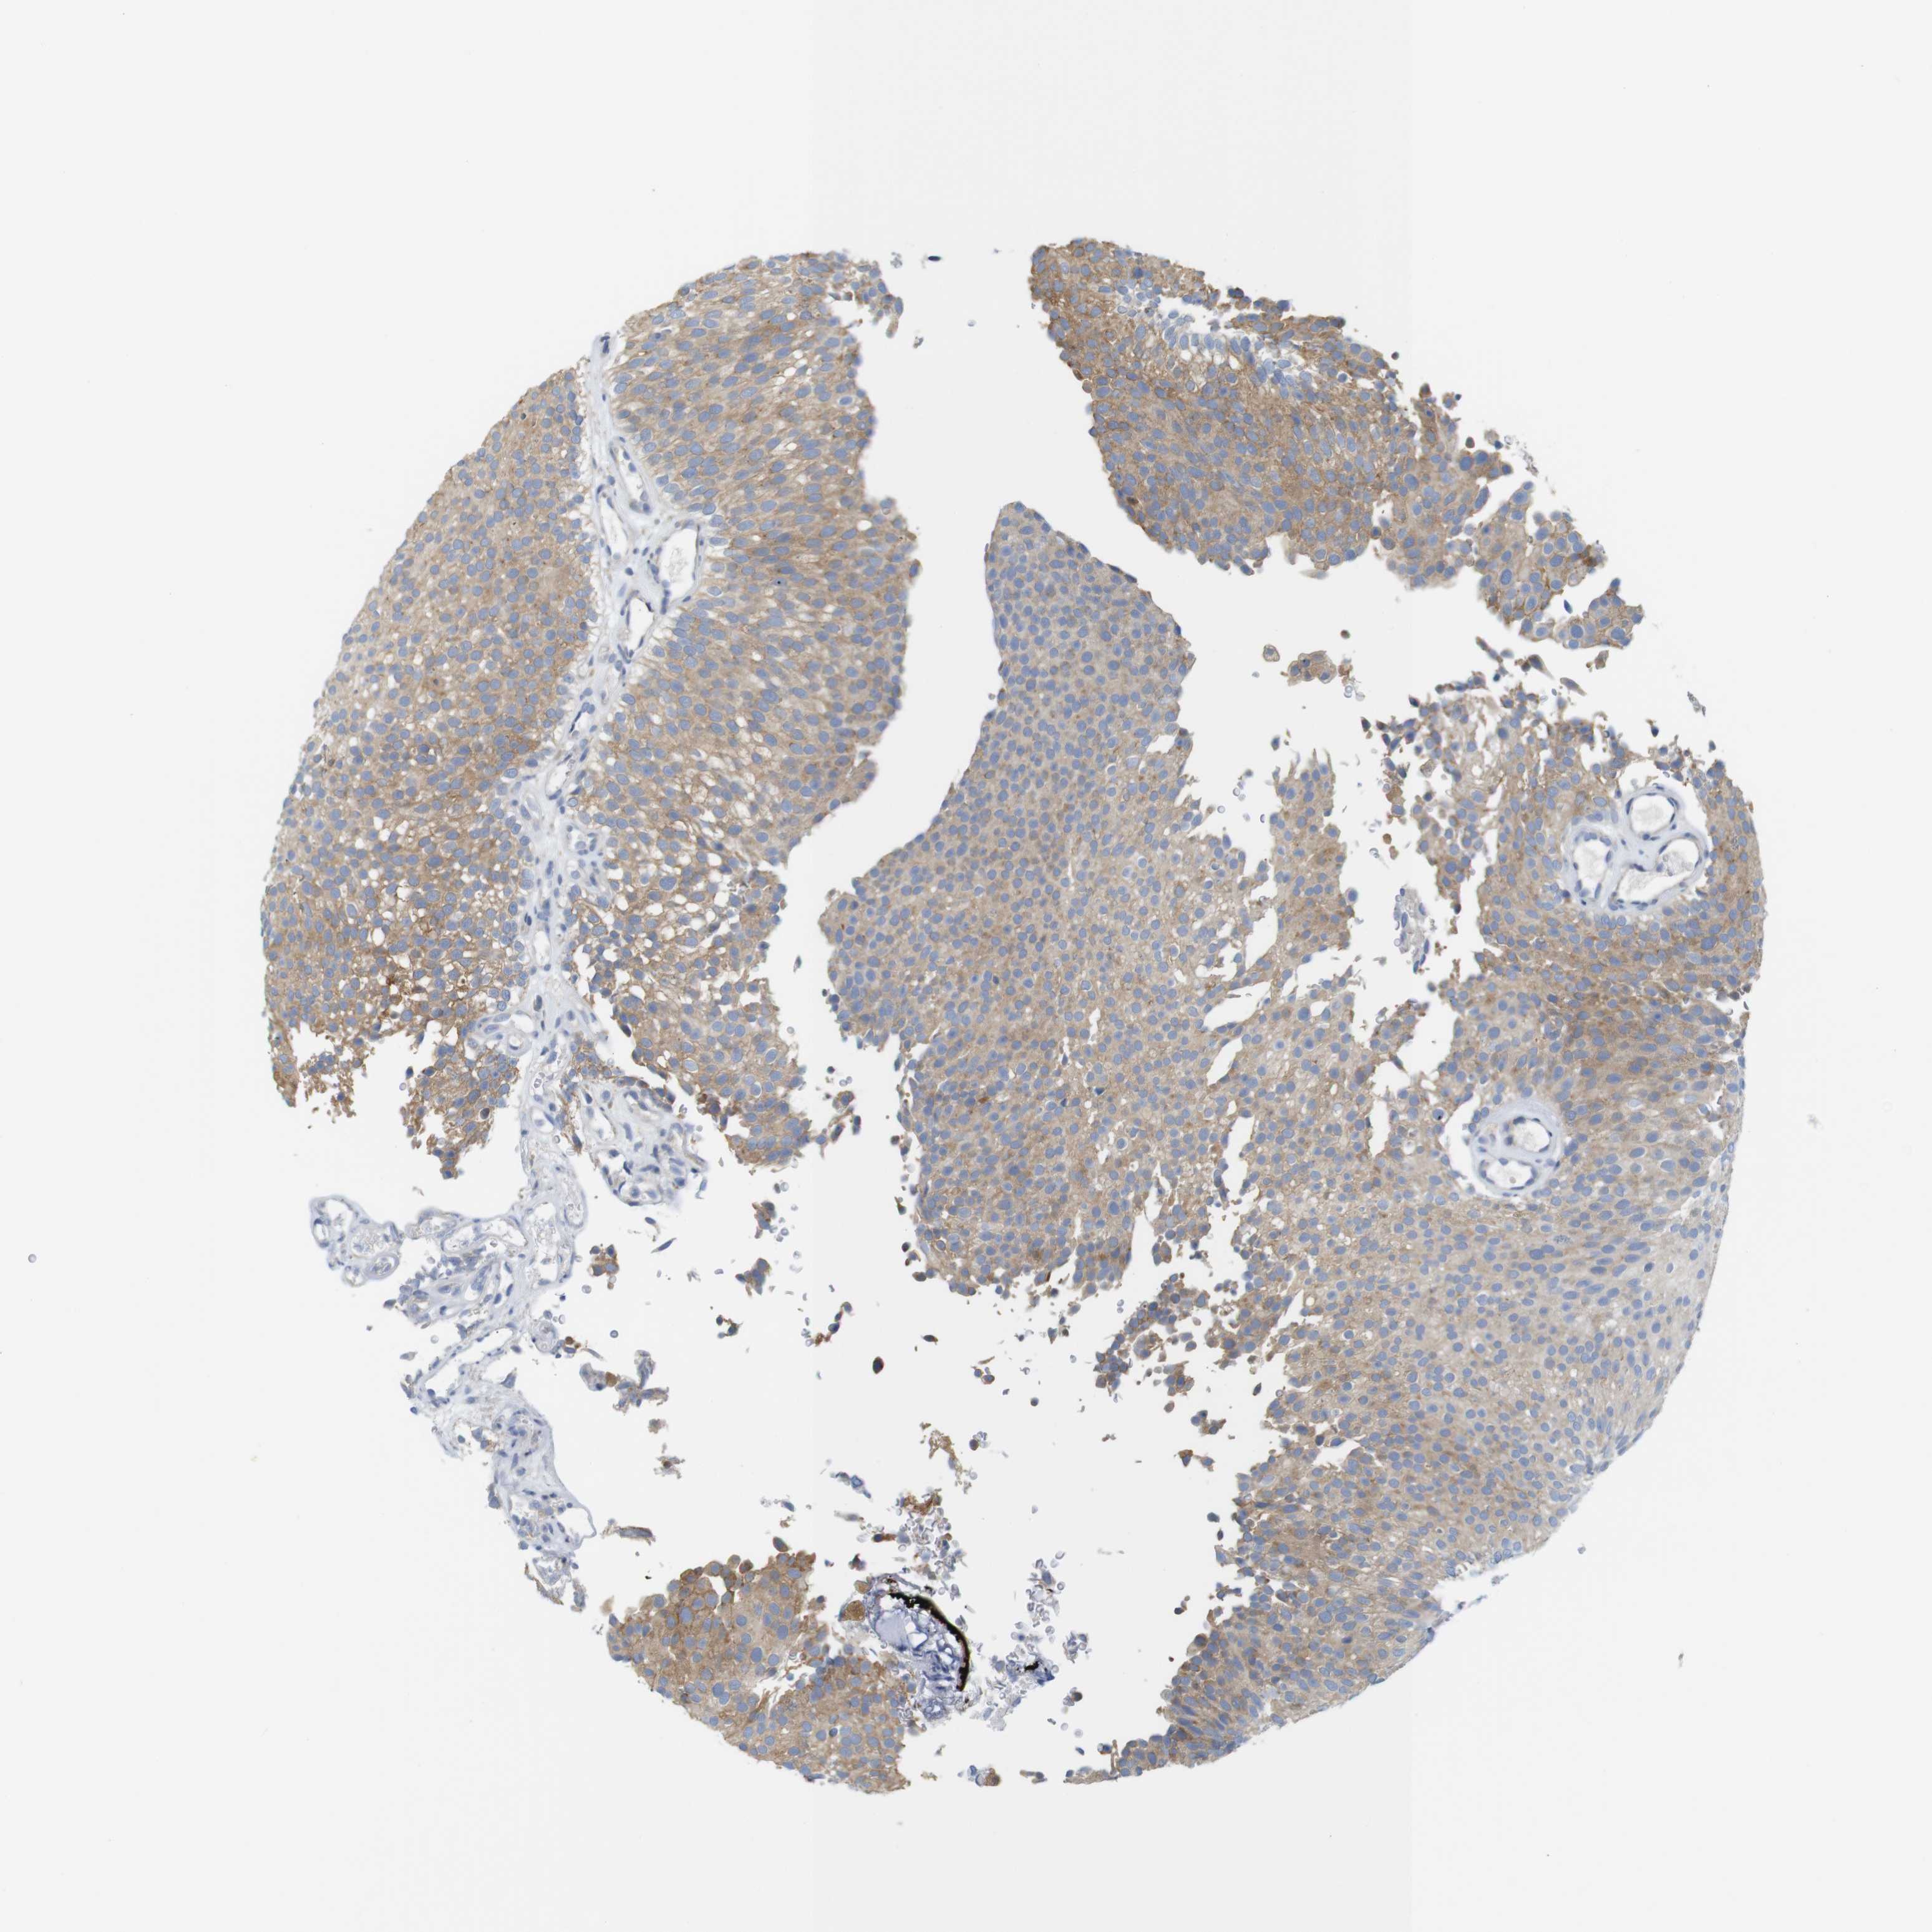

UROTHELIAL CANCER - Protein expressioni

A mouse-over function shows sample information and annotation data. Click on an image to view it in a full screen mode. Samples can be filtered based on level of antibody staining by selecting one or several of the following categories: high, medium, low and not detected. The assay and annotation is described here.

Note that samples used for immunohistochemistry by the Human Protein Atlas do not correspond to samples in the TCGA dataset.

Antibody stainingi

Antibody staining in the annotated cell types in the current human tissue is reported as not detected, low, medium, or high, based on conventional immunohistochemistry profiling in selected tissues. This score is based on the combination of the staining intensity and fraction of stained cells.

Each image is clickable and will lead to virtual microscopy that enables deeper exploration of all samples and also displays staining intensity scores, fraction scores and subcellular localization as well as patient and tissue information for each sample.

Antibody HPA013994

Antibody HPA013995

Staining

High

Medium

Low

Not detected

Intensity

Strong

Moderate

Weak

Negative

Quantity

>75%

75%-25%

<25%

None

Location

Nuclear

Cytoplasmic/membranous

Cytoplasmic/membranous,nuclear

Urothelial carcinoma, Low grade

Urothelial carcinoma, High grade